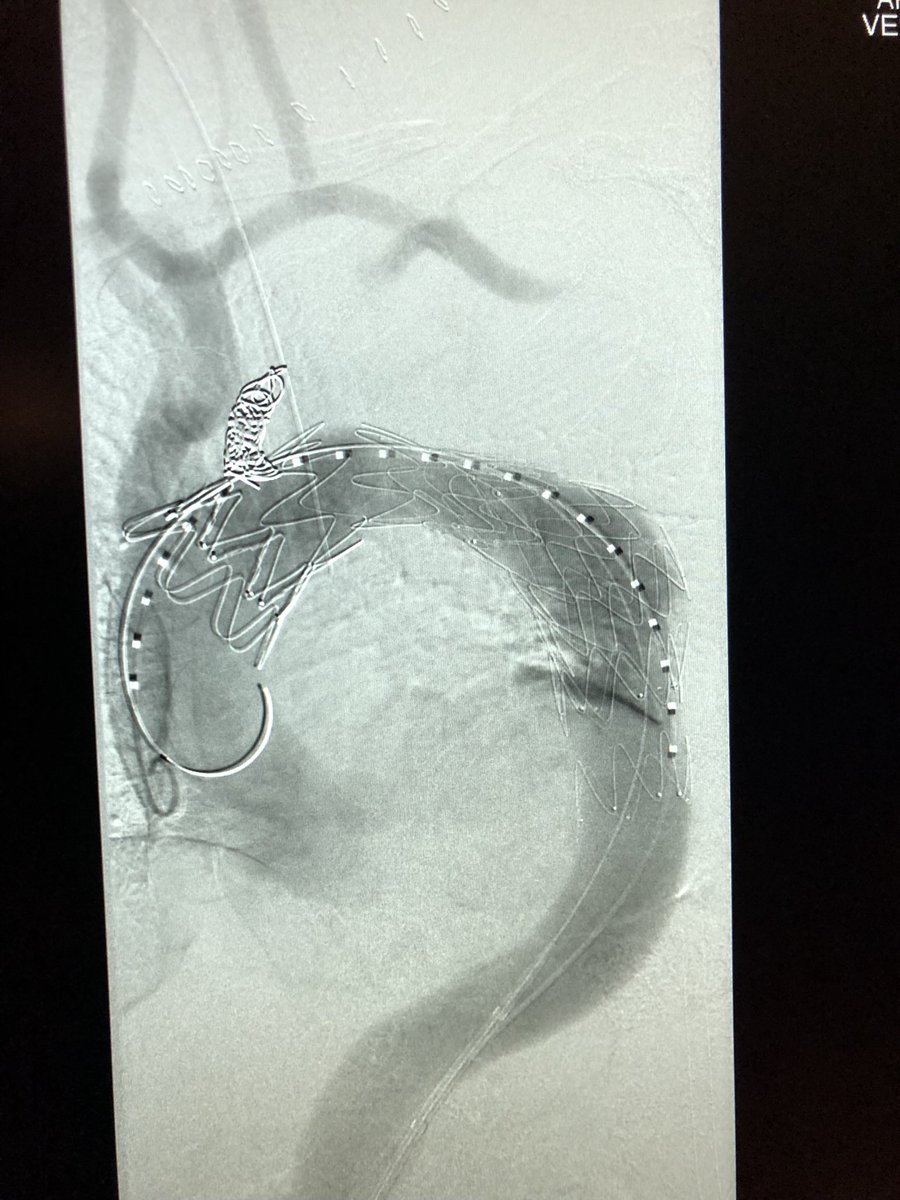

Live from #TCVCG 7cm arch aneurysm, right carotid to left subclavian bypass, left carotid transposition, TEVAR with @CookEVAR alpha. Courtesy of crezayat and bbrener

Live from #TCVCG 7cm arch aneurysm, right carotid to left subclavian bypass, left carotid transposition, TEVAR with @CookEVAR alpha. Courtesy of <a href="/crezayat/">crezayat</a> and <a href="/bbrener1/">bbrener</a>